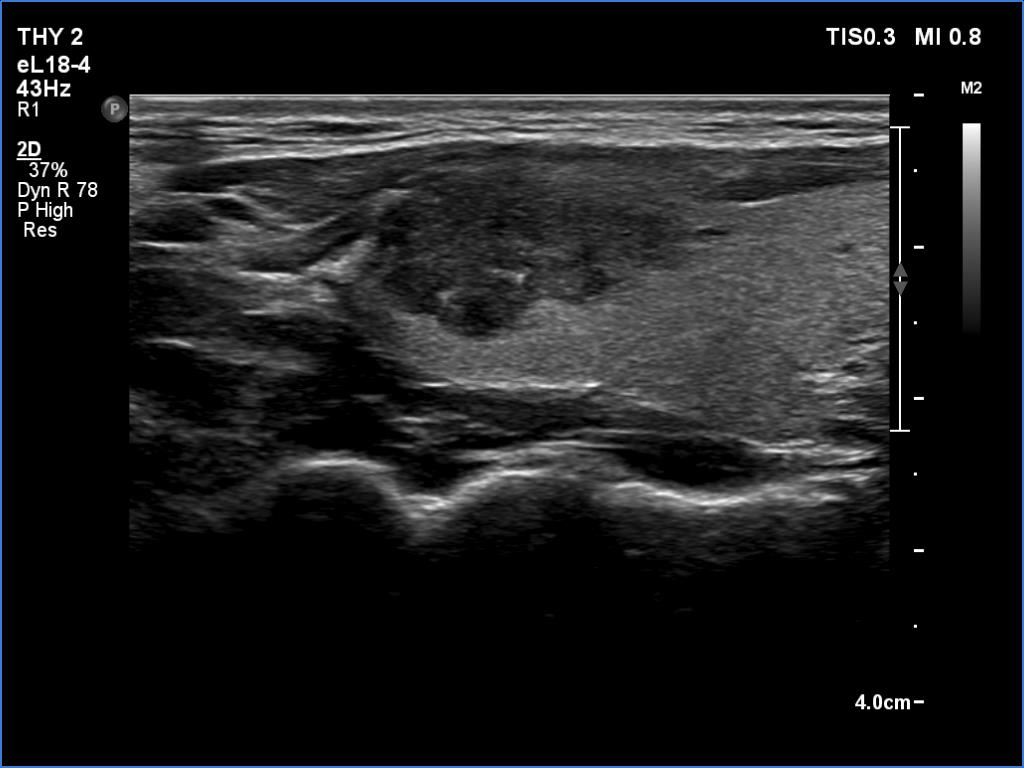

Ultrasonography. The thyroid was echonormal and presented two discrete lesions in the right lobe. The larger, upper one showed irregular margins, abutting and bulging contours and had back wall figures. The intranodular vascularization was significantly increased. The smaller lesion had microcalcifications and presented taller-than-wide shape.

Comment. It is worth thoroughly analyzing the intranodular echogenic figures. These are partly linear and most of them are related to tiny ventral cystic areas.